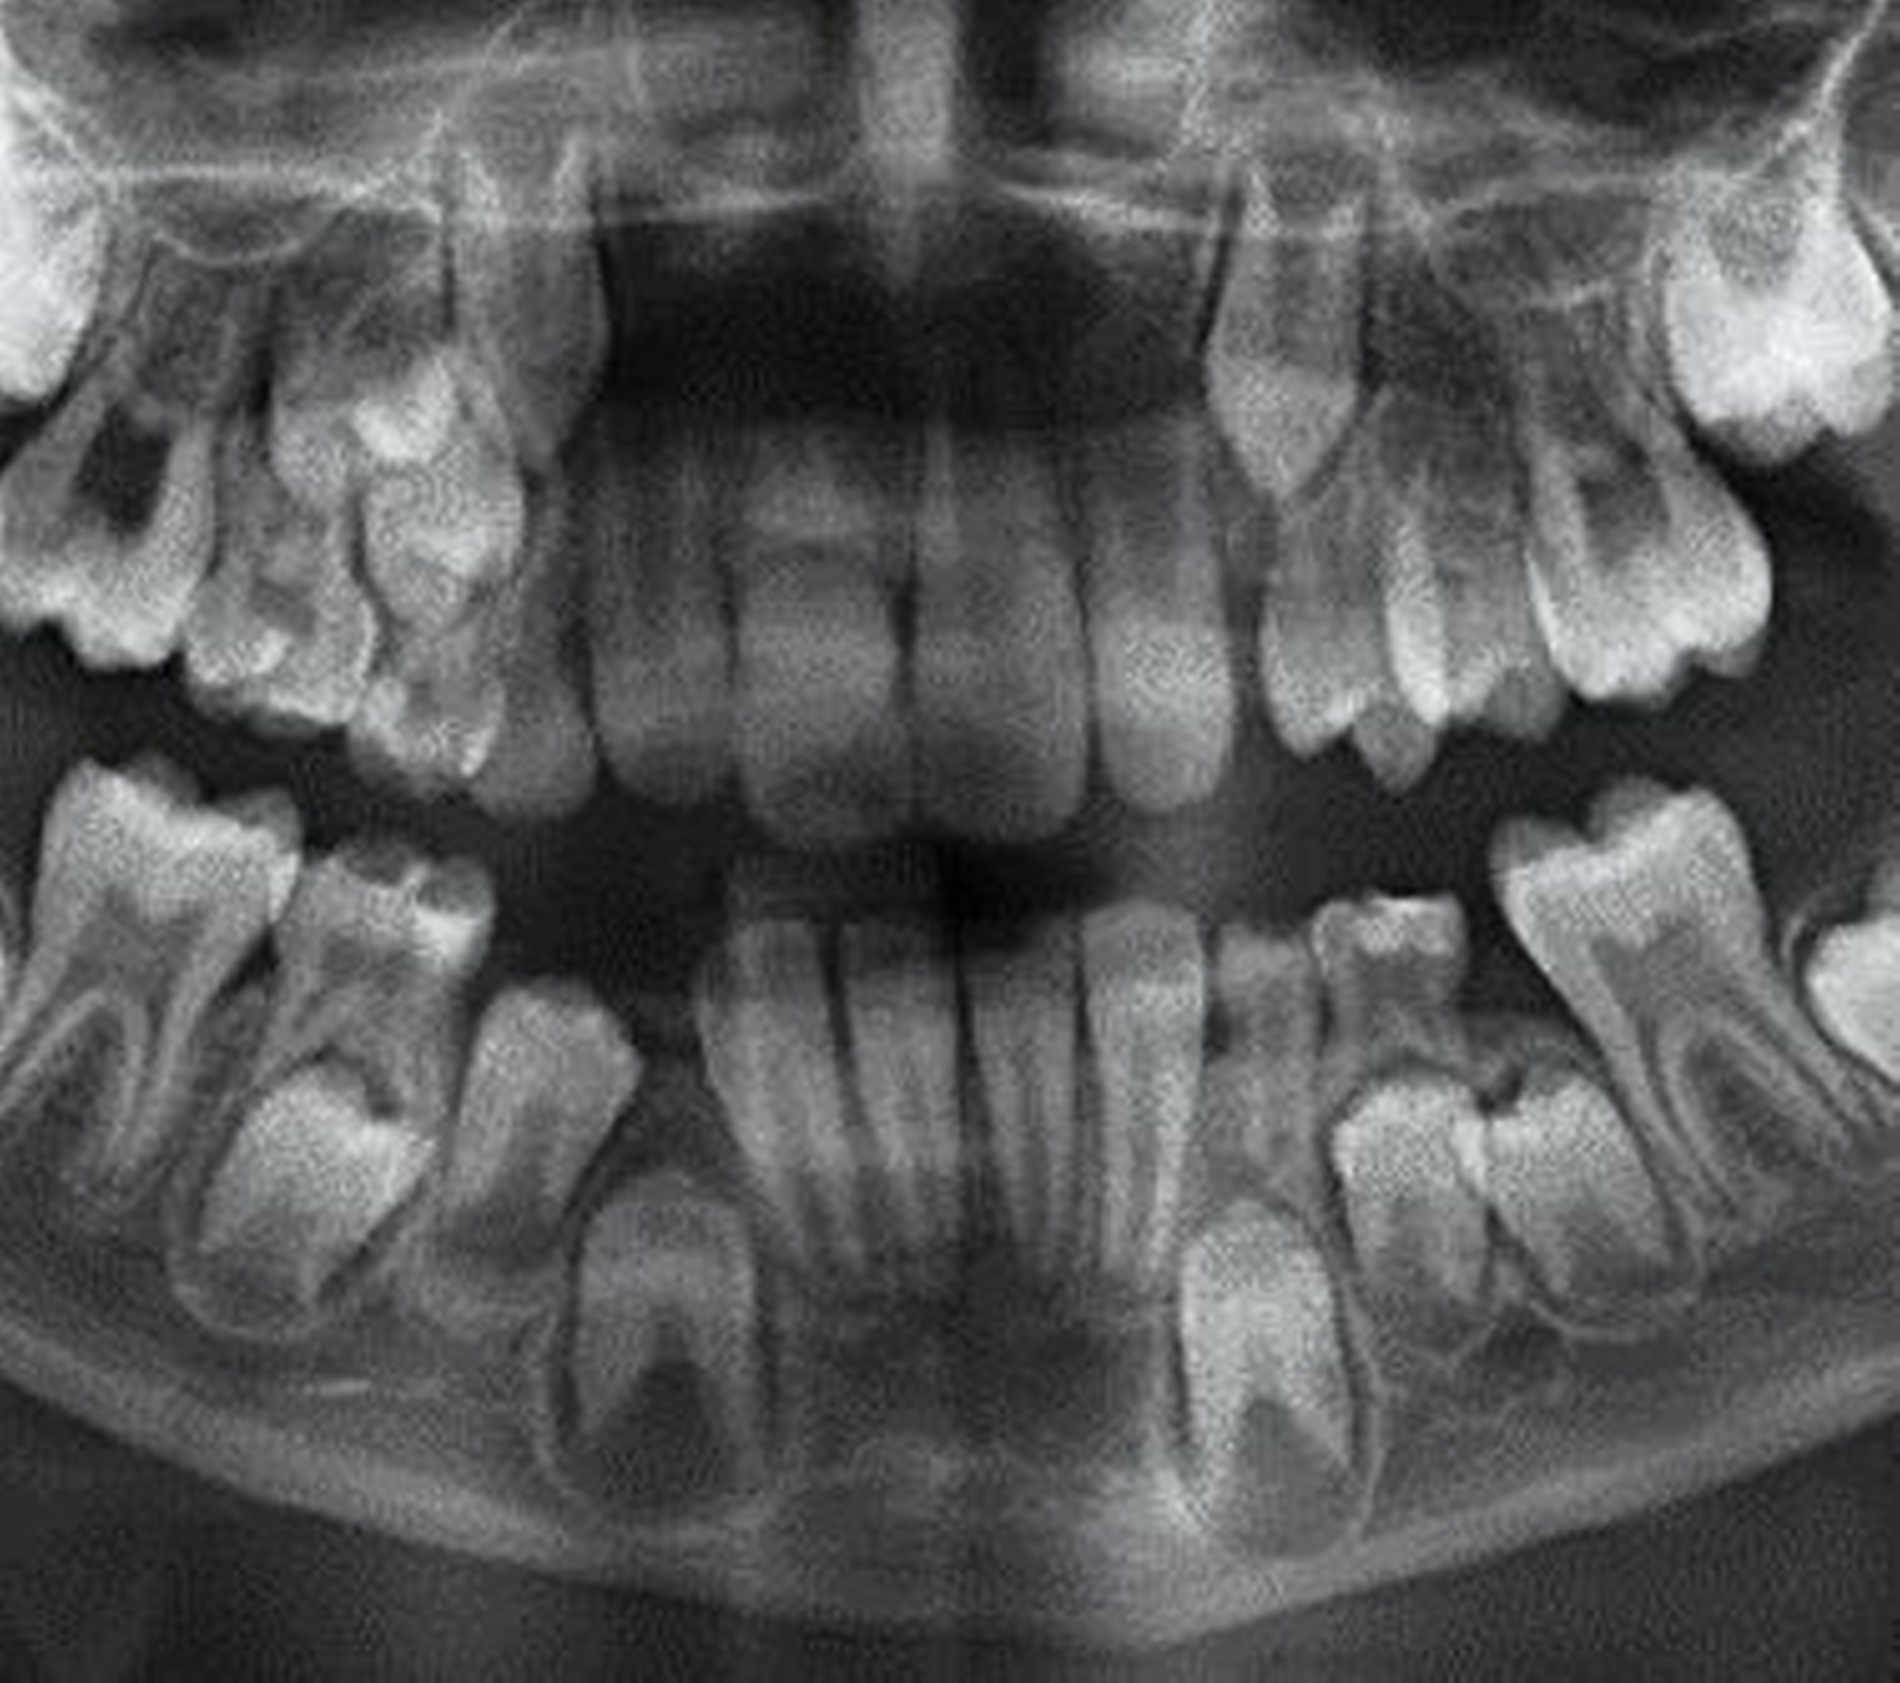

Abbildung 4 zeigt eine Milchzahn-Transplantation im frühen Wechselgebiss bei einem achtjährigen Mädchen bei nahezu vollständiger Ersatzresorption des Zahnes 11 nach Avulsion und Replantation. Trotz des sehr guten Zustands des Milchzahntransplants im Alter von zwölf Jahren entschied man sich in Rücksprache mit den Kollegen der Kieferorthopädie für die Prämolaren-Transplantation als eine zuverlässige Versorgung mit Überlebensraten von im Mittel 96,7 Prozent nach 8,75 Jahren [Akhlef et al., 2017]. Die Planung der Prämolaren-Transplantation sollte dabei immer in enger Absprache mit der Kieferorthopädie erfolgen, um zu klären, ob die Entnahme eines Prämolaren vertretbar und welche Entnahmestelle die geeignetste ist.